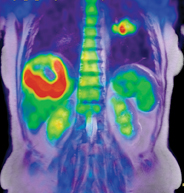

A liver tumor in an adult female using Philips Ingenuity TF PET/MR.

The addition of magnetic resonance (MR) imaging and spectroscopy to positron emission tomography (PET) is more expensive and more technically challenging compared with PET/computed tomography (CT). PET/CT is successful because the inclusion of CT has major advantages: accurate lesion localization, the identification of non-PET avid lesions and effective attenuation correction in a rapid, efficient combined examination. The addition of CT is particularly valuable for lungs and liver, where fluorodeoxyglucose (FDG) PET is limited by spatial resolution and relatively low target-to-background differential biodistribution. Presumably, PET/MR may disclose unique important diagnostic and prognostic information in selected patient groups.

What are potential advantages for a hybrid PET/MR system? As CT improves detection of lung and liver lesions compared with FDG PET alone, MR offers substantial advantages in the brain, spinal cord and prostate, along with advantages competitive with CT for liver lesion detection and characterization. While CT may have an edge over MR for cortical bone evaluation, MR is superior to CT for bone marrow imaging. Either can be satisfactory for bone and marrow evaluation when combined with PET.